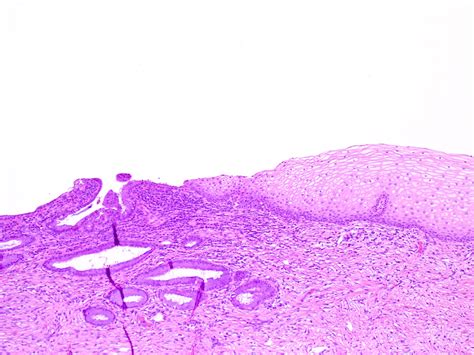

The cervix, the lower part of the uterus, is covered by two distinct case of cells. The endocervix (the inner canal) is lined by delicate, mucus-producing glandular cells, while the ectocervix (the outer component seeable during a pelvic exam) is extend by tough, squamous cells. Ectropion of cervix uteri occurs when the glandular cells from the interior of the cervical duct grow outward onto the surface of the ectocervix.

Because these glandular cell are course lean and more fragile than the squamous cells that normally continue the outer cervix, the area can seem red, inflame, or raw. This visual appearing is why it is sometimes incorrectly referred to as a "cervical wearing", though there is no actual erosion or harm to the tissue.